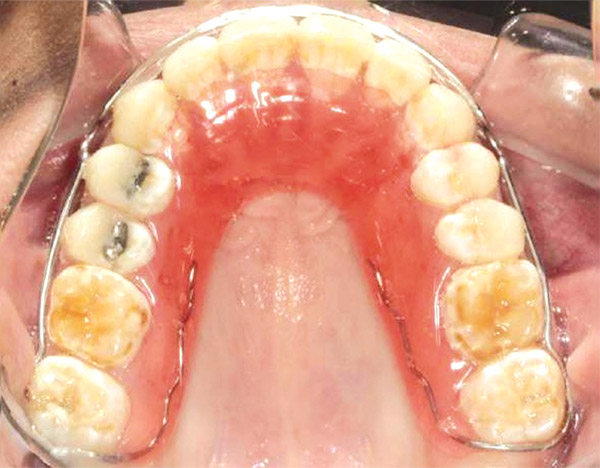

Figura 6. Oclusal superior.

En las fotografías intraorales se muestra la fluorosis dental Tf4 y Tf7, las relaciones molares clase II molar y canina bilateral (Figura 3 y 4), el apiñamiento severo superior e inferior, con el órgano dental 35 en infraoclusión. El overbite aumentado y las líneas medias dentales no son coincidentes (Figura 5), las formas de arco superior e inferior son cuadradas (Figura 6 y 7).